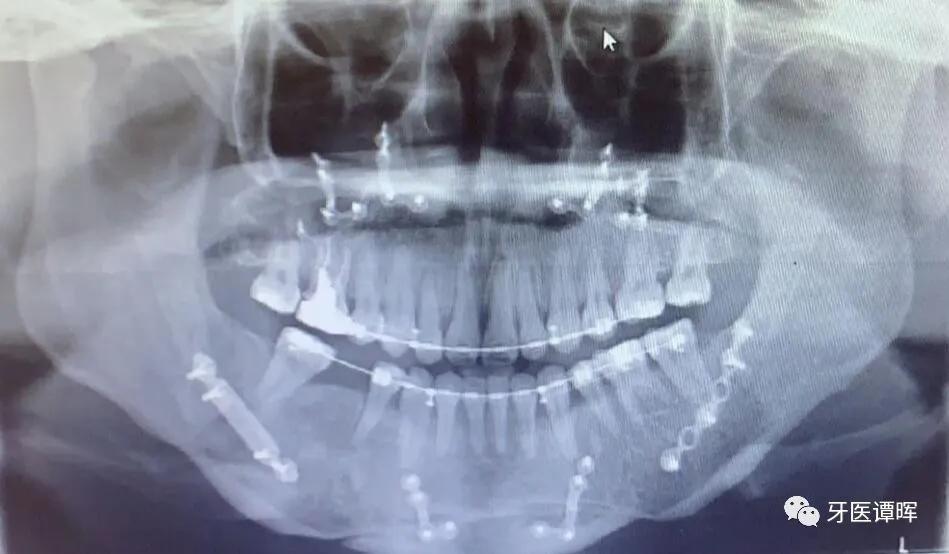

拍 片

一般的龅牙矫正和地包天矫正都是要拍头颅侧位片,用于头影测量,得出相应的数据,就知道暴牙突出的根源所在,知道是牙齿的原因还是骨骼的原因,决定是否则拔牙的重要依据。

其它情况下也可能要拍片,医生根据实际情况而定。